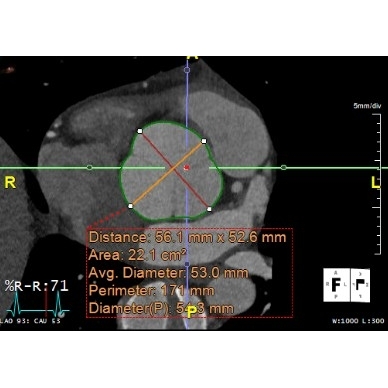

Screening electrocardiogram revealed atrial fibrillation with a ventricular rate of 94 beats per minute Case Photo #1 , and a three-day Holter monitor resulted in a 100 percent atrial fibrillation burden with an average heart rate of 110 beats per minute Case Photo #2 . A transthoracic echocardiogram showed severe aortic sinus and ascending aorta dilation to a maximum diameter of 5.10 centimeters (at his age, normal is considered 2.5 centimeters to 3.5 centimeters). It also revealed a mildly dilated left ventricle with normal wall thickness, systolic function, and diastolic function. It showed mild right ventricle dilation with normal systolic function. Mild aortic, mitral, tricuspid, and pulmonic regurgitation was present. The inferior vena cava was mildly dilated. Computerized tomography angiography confirmed the presence of a dilated aortic root with a maximum diameter of 5.30 centimeters at the sinus of Valsalva Case Photo #3 . On review of imaging records from his prior school, he received a screening transthoracic echocardiogram as a part of his pre-participation evaluation, which revealed the initial aortic root dilation. Subsequent workup at his previous school with a CT angiogram revealed a maximum diameter of the aortic root of 5.10 centimeters one year ago. Cardiac magnetic resonance imaging with and without intravenous contrast reiterated all findings as noted above and showed that the aortic size was normal above the level of the mid-ascending aorta Case Photo #4 . Computerized tomography coronary angiography was done about two months after the initial imaging listed above, which revealed no coronary artery atherosclerosis and revealed a maximum aortic root dilation of 5.60 centimeters Case Photo #5 . Based on these results, he had an aortic root z-score of 7.90 (normal variance is negative 2 to positive 2). (1-2)